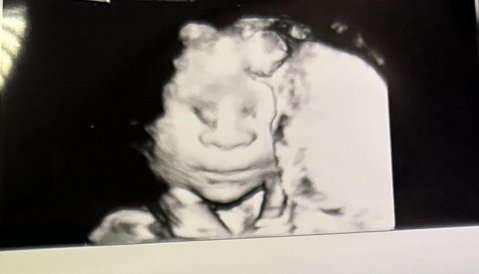

Здравейте дами, надявам се всички да сте добре, както и бебчетата. Аз се включвам да кажа, че днес мерихме размера на шийката и гледахме плацентата, тъй като беше по задната стена и малко по-надолу. Шийката беше над 4см, а плацентата беше на около 8см разстояние. Исках да направим 4д снимки, защото таткото не можеше да дойде с мен на прегледа и около 15мин боцках бебето и кашлях, да си извади ръцете от устата, но той упорито искаше да си смуче пръста. Също така се смяхме на това, че се прозя и си сложи ръката пред устата, доста възпитано Satisfied

Пускам ви снимчица с малка усмивка.